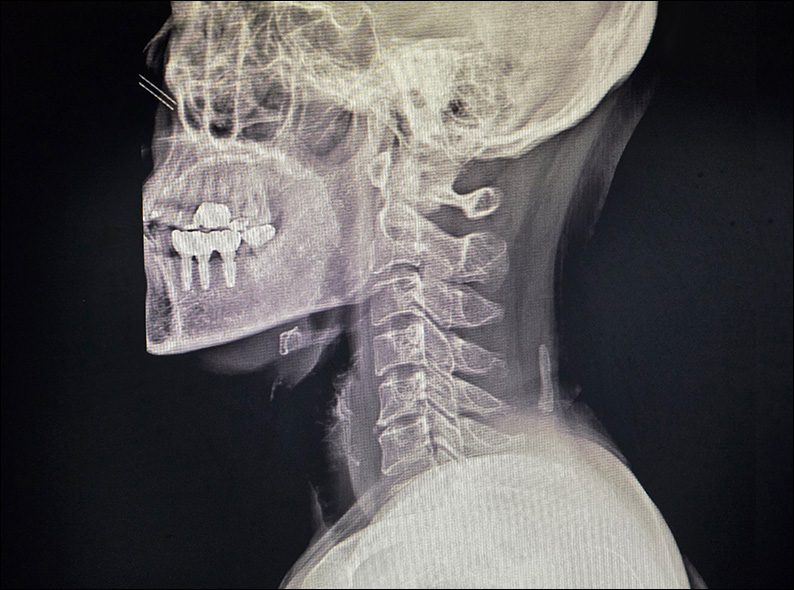

목덜미 통증으로 물리치료와 도수치료를 받았으나 악화되어

어깨와 팔의 방사통과 손 저림까지 발생한 환자.

경추의 C자형 커브가 일자로 변형되고 뼈의 퇴행성 변화도 관찰되는 상태